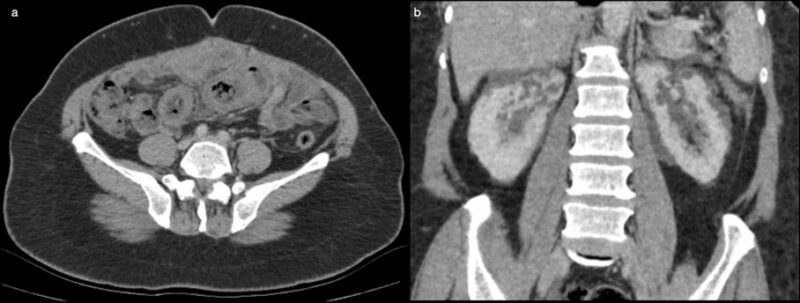

86-year-old woman presenting for abdominal aortic aneurysm surveillance

An 86-year-old woman with a history of an abdominal aortic aneurysm presented for surveillance.

Published Date: February 17, 2026

Tags:

Abdominal

,

Angiography

Body

CT

Vascular